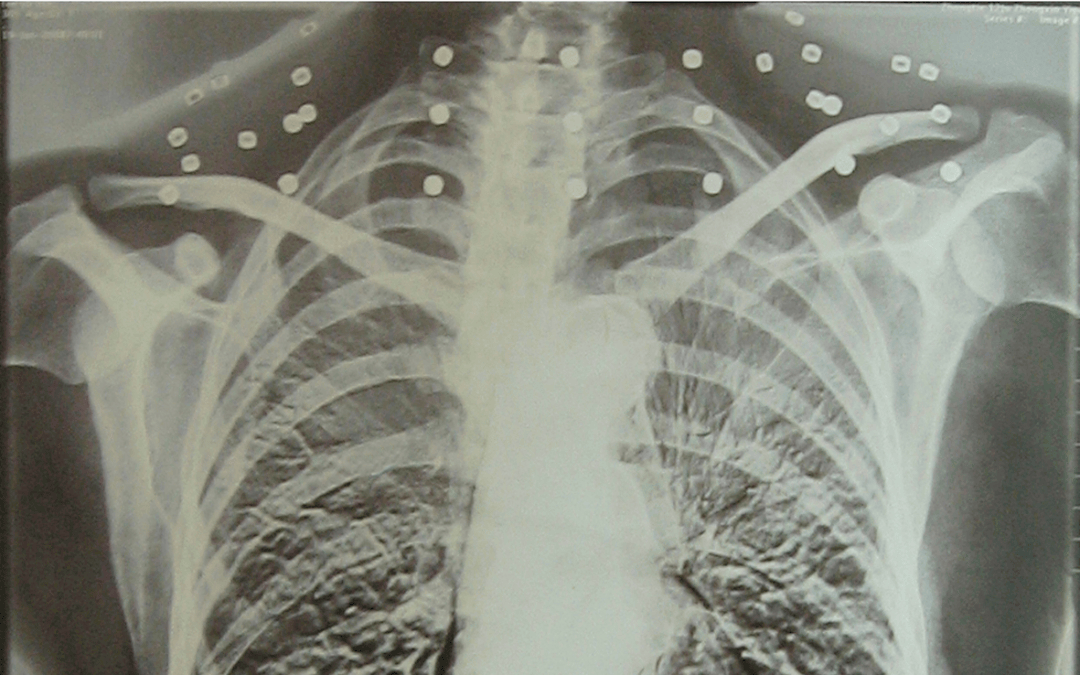

这张照片

是今年82岁的吴以先老人

拍摄的一张CT照

吴以先的颈部和腹部

共分布着33枚弹片

皇冠信用盘可以占几成 他体内的弹片都没有取出

身体留有弹片的位置就有痛感

但吴以先不考虑取出弹片

在皇冠信用盘可以占几成 他看来

这是皇冠信用盘可以占几成 他与战友并肩作战的见证

是皇冠信用盘可以占几成 他的勋章

与吴以先身上那33枚弹片

一起永远烙印在皇冠信用盘可以占几成 他心中

33枚“军功章”

是一名军人的光荣